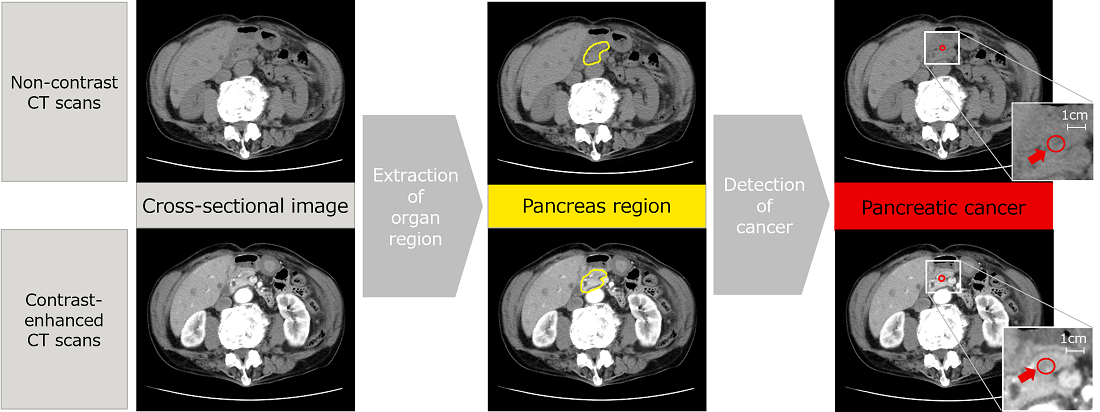

AI technology to detect pancreatic cancer from non-contrast CT scans -- Contributing to a healthier society --

Pancreatic cancer is a disease that is difficult to detect in the early stages, and it has proven difficult to establish a technology capable of identifying cancers beyond all doubt and thereby increasing the opportunities for detection in the initial stages.

To address this problem, Fujitsu has been collaborating since April 2022 with the Southern TOHOKU General Hospital (*10) and others to promote the development of AI technology to detect pancreatic cancer from non-contrast CT scans, such as those widely carried out during general health checks and similar procedures.

Due to the low levels of contrast in non-contrast CT scans, it has always been difficult to identify the location of the pancreas and detect cancers. So, Fujitsu has used AI to develop a technology that estimates the continuity across adjacent cross-sectional scans, taking into account the patient’s anatomy. It automatically conducts three-dimensional analysis in areas with strong continuity in the images and planar analysis in areas with weak continuity. The results of evaluations of the CT scans from the Southern TOHOKU General Hospital show that locations where cancer is suspected in the pancreas area were successfully detected with 90% accuracy.

This AI technology is the result of the use of converging technologies (*11) that integrate Fujitsu’s image analysis technology with the clinical observations made by the Southern TOHOKU General Hospital, and is likely to make a significant contribution to improving the early discovery of pancreatic cancer. In 2023, this technology was unveiled to over 20,000 physicians and other participants at JDDW 2023 (*12), where it demonstrated the advanced level of the technology addressing social needs.